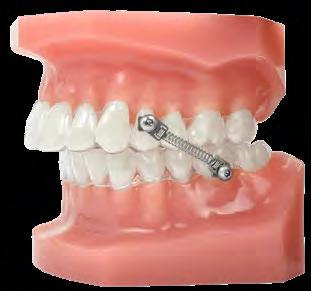

DISPOSITIVO DE CORRECCIÓN

DEFINITIVA EN EL SILLÓN DENTAL

CS®5 Spring

• Carga Instantánea

• Fuerza Constante Twist-Lock Pivot

•

• Diseño de una pieza Instalación simplificada

• Rendimiento Mejorado Lápiz Allen Magnético

• Colocación más segura

• Rápida instalación Tornillo híbrido con Nylok™

• Resistencia al Aflojamiento

• Ajuste más seguro